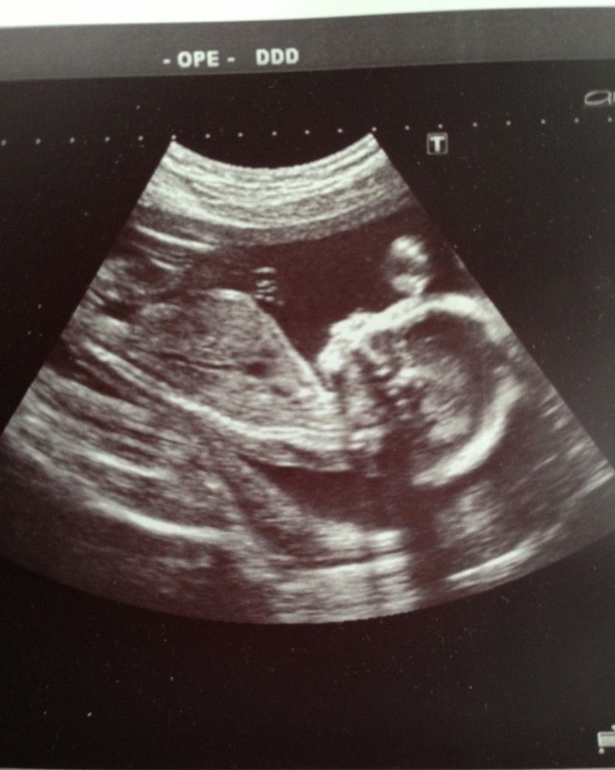

второе УЗИ

О хорошемСпешу поделиться..Вот сходили мы с мужем на второе УЗИ.все хорошо, малыш развивается весим 380г..отклонений нет.Сыночек подвижный...Нам с папой ручкой помахал..муж аж покраснел..такой радостный что впервые увидел сынулю..В общем растем потихоньку.